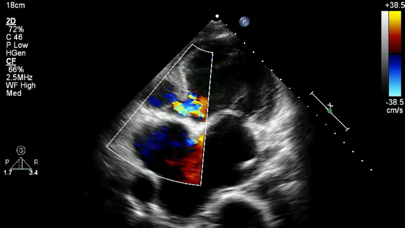

This app is a Lite version of CARDIO3® Comprehensive Atlas of Echocardiography (ISBN 80-969114-8-1) - reference/learning tool for cardiologists, cardiac surgeons, internists, other physicians, and sonographers evaluating

echocardiograms for ultrasound diagnosis.